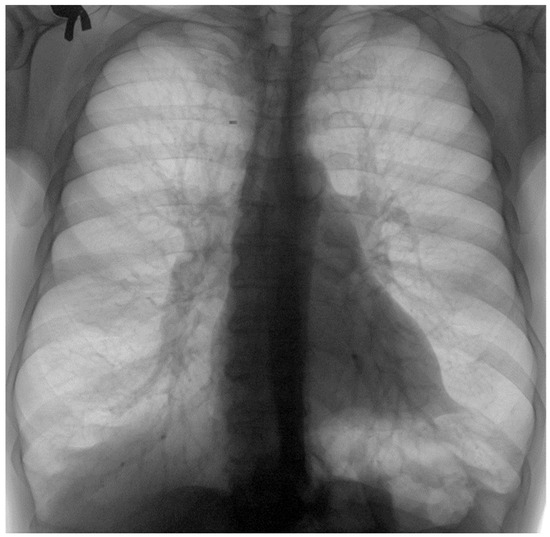

The chest radiograph of healthy lungs on which the fractal analysis was performed is shown in Figure 29a. Aside from the high-quality imaging provided by CT procedures (Figure 29a,b), the picture evaluation assured quantitative information regarding various structural features, such as the fractal dimension and lacunarity.

Figure 30 shows the 2D box-counting algorithm with the local fractal dimension calculation for the healthy-lung CT image. Figure 31 displays the 3D graphical representation of the voxels present in the CT lung image of healthy patient. Table 7 presents the calculated values for the fractal dimension and the lacunarity of the CT image evaluations for the healthy patient.

Table 7 shows the known fractal indicators, such as the fractal dimension of the CT image of the left lung, dHL = 1.6410 ± 0.3577, and lacunarity Λ = 0.0475; and the fractal dimension of the right lung, dHR = 1.6318 ± 0.3598, and lacunarity, Λ = 0.0486.

Figure 29. (a) Healthy lung image, (b) binary version, (c) mask for the left lung, (d) mask for the right lung.